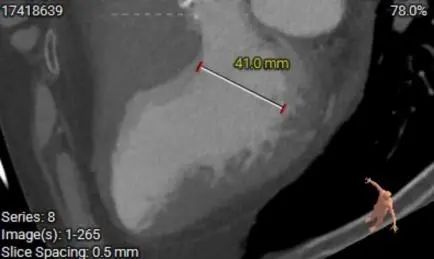

钙化分布:HU850:852.2m³

手术策略与讨论

Typ1型二叶瓣,极重度钙化,瓣膜锚定力可,预估瓣膜形态影响较大,钙化分布于瓣叶上,结 合流出道形态及瓣上多平面分析,预估瓣膜释放后下滑风险较高,少量偏多瓣周漏可能。

左右冠开口高度可,综合瓦氏窦内径、窦管交界内径等因素考虑,冠脉风险较低 。

计划使用22mm球囊进行有扩张,瓣膜进行释放,结合流出道形态及瓣上多平面分析,26瓣膜进行释放,结合流出道形态及瓣上多平面分析,采取释放高度瓣膜下3mm左右。